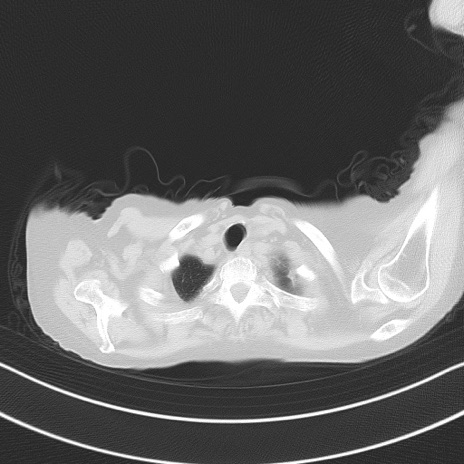

横断像

他院CT